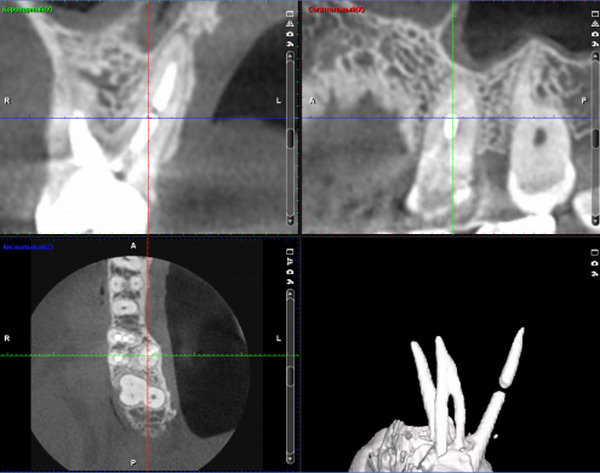

Потемнение зуба и беспокойство говорят о хроническом воспалении (периодонтит).

Обратитесь к врачу на очный прием, данное лечение проводится в несколько посещений.